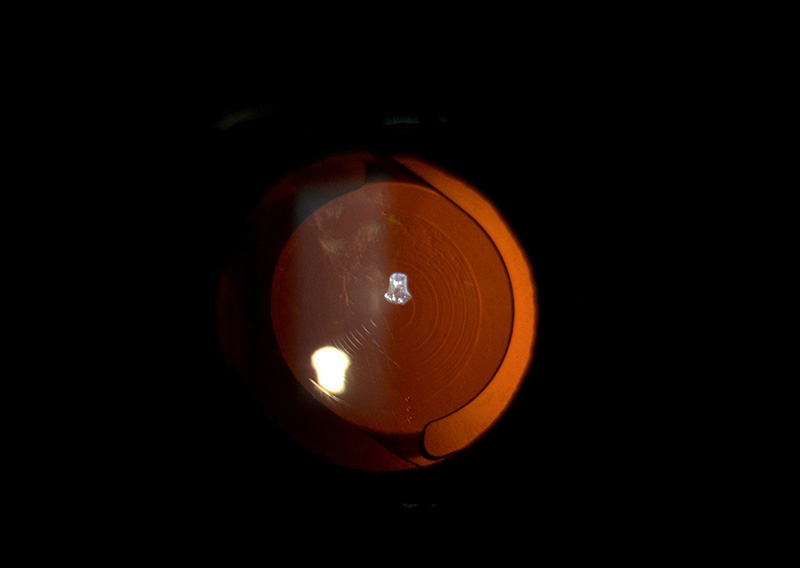

Refracting after a Vivity IOL is different than a regular refraction.